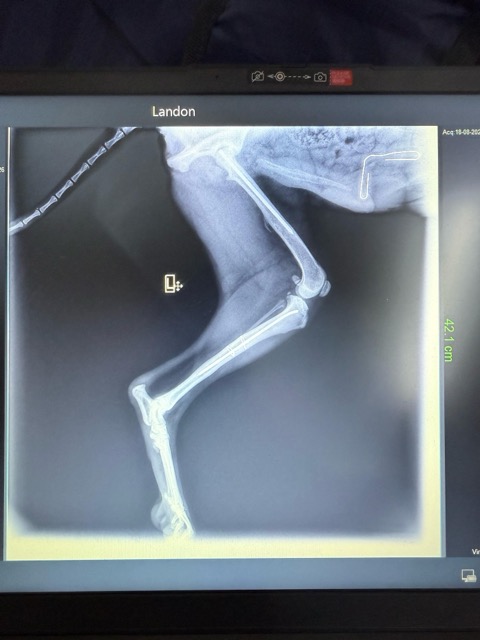

LANDON a été trouvé chiot et blessé sur la route (patte cassée), au Liban. Recueilli et soigné par le Refuge de l’association BETA LEBANON.